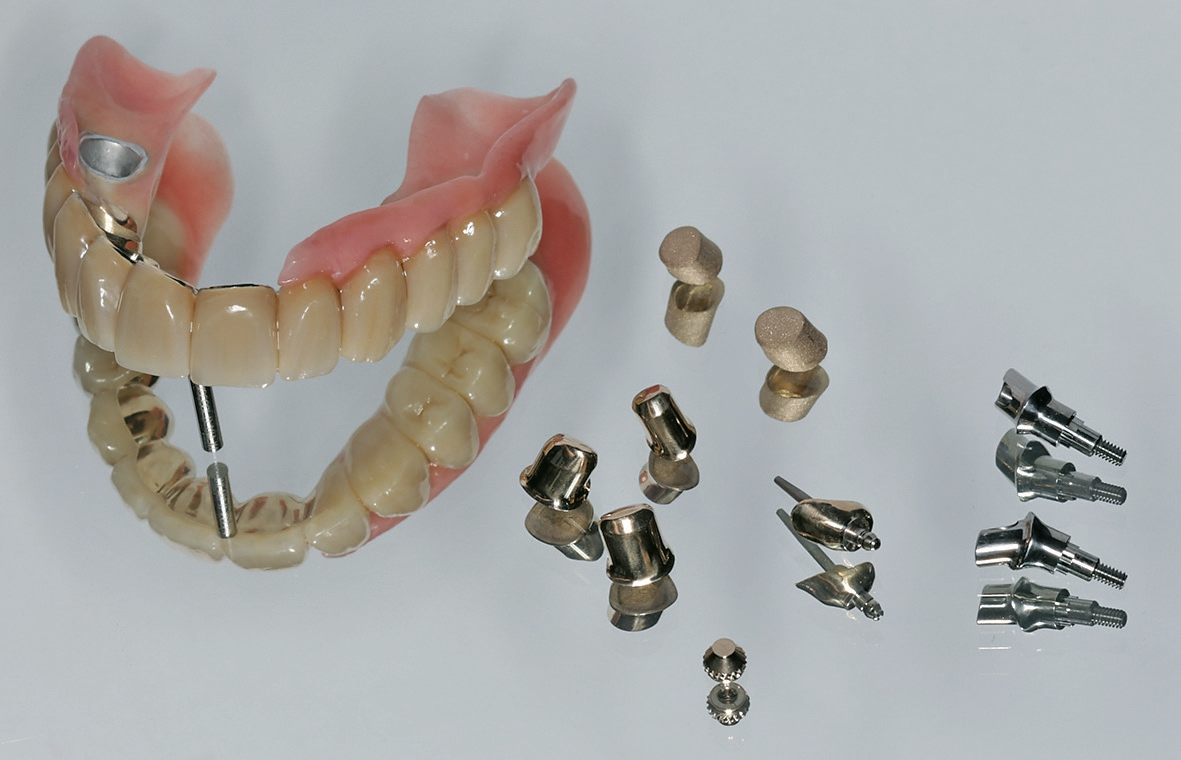

In einem nächsten Schritt wurden die Primärteile provisorisch fixiert und zusammen mit den Implantaten und den Schleimhautarealen überabgeformt (ImpregumTM, 3M) zur Herstellung des Meistermodells (Abb. 15). Die Position der Implantate wurde mittels „Verification Stent“ rückkontrolliert und die vertikale und horizontale Kieferrelation intraoral mittels Handbissnahme verschlüsselt. Aufgrund der nicht unerheblichen Achsendivergenz zwischen den Implantaten und den natürlichen Pfeilerzähnen wurde entschieden, die Implantate anstelle von konfektionierten Einzelelementen mit individuellen CAD/CAM-Teleskopkronen (Atlantis Abutments, Dentsply Sirona, Wals bei Salzburg, Österreich) zu versorgen. Konfektionierte Einzelelemente wären durch die Achsendivergenz einem erhöhten Verschleiß unterzogen gewesen, was wiederum mit einem gesteigerten Nachsorgebedarf verbunden gewesen wäre. Nach mehreren Set-up-Einproben konnte schließlich auch das Sekundärgerüst hergestellt werden. Sämtliche Sekundärteile wurden dabei als Vollgussteile designt und mit dem Modellgussgerüst verklebt, mit Ausnahme der Sekundärteile für die Implantatteleskopkronen, welche zur Sicherstellung der Passivität intraoral verklebt werden sollten (Abb. 16 u. 17). Sowohl Primär- als auch Sekundärteile wurden für eine höhere Härte während 30 min bei 400°C vergütet. Anschließend konnte das geschlüsselte Set-up und auf das Gerüst aufgepasst werden. Um die Pfeilerzähne wurde die Prothese offen gestaltet, um eine natürliche Umspülung der Pfeilerzähne zu ermöglichen. Auf ein Palatinalband konnte aufgrund der guten Kammverhältnisse und des breiten Unterstützungspolygons verzichtet werden. Nach einer letzten klinischen Einprobe konnte die Prothese durch den Zahntechniker individualisiert und fertiggestellt werden (Abb. 18).

Die Teleskopkronen und die Wurzelstiftkappe wurden mit Glasionomerzement (KetacTM Cem, 3M) sukzessive einzeln eingesetzt. Die Implantatteleskopkronen wurden mit einem Anzugsdrehmoment von 35 Ncm festgeschraubt und mit weißer Guttapercha und Glasionomerzement (KetacTM Bond, 3M) verschlossen. Nach einer Tragedauer von einer Woche, in der sich die Prothese einlagern konnte, wurden die Sekundärteile der Implantatteleskopkronen und die Matrize der Wurzelstiftkappe intraoral verklebt (Super-T, American Consolidated Manufacturing, Conshohocken, USA) (Abb. 19).